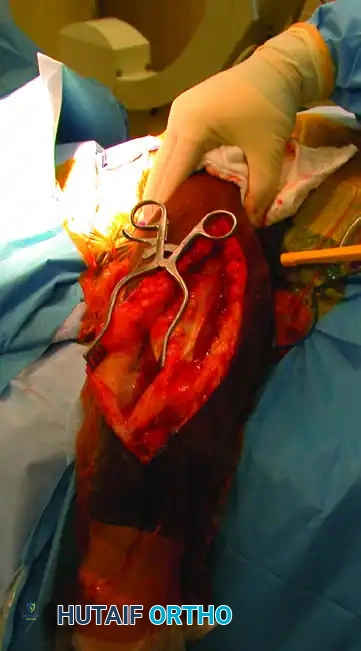

Fracture Reduction and Provisional Fixation

- Place a single bone clamp (e.g., a pointed reduction forceps or Verbrugge clamp) on the proximal and distal fragments. Ensure these clamps are placed far away from the fracture site to control the fragments and simultaneously reflect the triceps.

- Avoid Circumferential Stripping: Never pass clamps circumferentially around the bone if it requires stripping intact soft tissue attachments.

- After meticulous débridement of the fracture site, achieve anatomic reduction.

- For oblique or spiral fractures, insert an interfragmentary lag screw for provisional absolute stability.